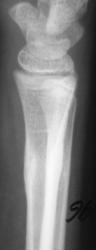

Пациент направлен в рентгеновский кабинет врачом хирургом, по поводу болей в дистальной трети предплечья. Пациент и его родители утверждают, что травмы не было.

Снимки с более высокой степенью разрешения.

Определяются локальные оссифицированные периостальные наслоения в н/3 диафиза лучевой кости, что-то наподобие дефекта со склеротическим контуром по передней поверхности кости. У меня три варианта: 1 - консолидированный перелом лучевой кости; 2 - патологическая перестройка (читала у Рейнберга, может встречаться в лучевых и локтевых костях, выглядит как консолидированный перелом); 3 - первично-хр. остеомиелит.

Больше похоже на срастающийся перелом.

Но т равмы не было. Чем может быть вызвана "одностороняя реакция надкостницы"?

Меня тоже смущает, и очень. Отправляйте к детским онкологам, пусть они контролируют. Основание: диафиз лучевой кости бульбообразно расширен ("поддут"), структура кости уплотнена муфтообразно/"пояском", менее выраженные, чем по переднему стенке кости, но аналогичные изменения отмечаются и по задней стенке диафиза, плюс периостальная реакция в прямой проекции.